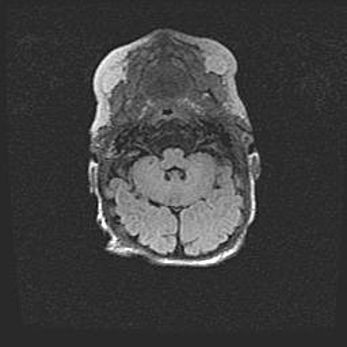

Церебральная ишемия II.

Возраст: 5 дней

Вес: 3400 г

Пол: женский

Окружность головы: 35 см

Срок гестации: 39 недель

Церебральная ишемия – это заболевание, характеризующееся недостаточностью (гипоксией) либо полным прекращением (аноксией) снабжения мозга кислородом по причине закупорки одного или нескольких сосудов. Это приводит к  что метаболическим расстройствам различной степени тяжести в тканях головного мозга, развитию коагуляционных некрозов и гибели нейронов.